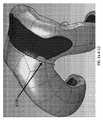

開示されるインプラント及びインプラントシステムは、任意の数の患者特異的インプラントコンポーネントと、任意の数の非患者特異的インプラントコンポーネントとを含むことができる。例示的インプラント又はインプラントシステムが図3A〜図3Cに示される。具体的には、図3Aは、患者特異的2コンパートメント型インプラントコンポーネント300と患者特異的1コンパートメント型インプラントコンポーネント310とを含む患者特異的人工膝関節全置換術インプラントシステムの写真を示す。双方のコンポーネントとも、それらの骨に面した表面及びそれらの関節に面した表面の双方に関して患者特異的である。図3B及び図3Cは、図3Aのインプラントを冠状面(図3B)及び矢状面(図3C)で示すX線像である。1.3 Multi-component implants and implant systems The disclosed implants and implant systems can include any number of patient-specific implant components and any number of non-patient-specific implant components. An exemplary implant or implant system is shown in FIGS. 3A-3C. Specifically, FIG. 3A shows a photograph of a patient-specific total knee replacement implant system that includes a patient-specific two-

特定の実施形態において、インプラント及びインプラントシステムは、インプラントコンポーネントの、例えば従来の1コンパートメント装置の患者特異的2コンパートメント装置との組み合わせ、又は患者特異的1コンパートメント装置の標準的な2コンパートメント装置との組み合わせを含み得る。かかるインプラントの組み合わせにより、標準的及び患者特異的の双方の特徴及びコンポーネントを含むインプラント又はインプラントシステムの柔軟な設計が可能となる。この柔軟性及び患者特異性のレベルにより、全ての靱帯の維持及び/又は正常な若しくはほぼ正常な患者キネマティクスの修復など、様々な最適化が可能となる。 In certain embodiments, the implant and the implant system are a combination of an implant component, for example, a conventional one-compartment device with a patient-specific two-compartment device, or a patient-specific one-compartment device with a standard two-compartment device. Can be included. Such an implant combination allows for a flexible design of an implant or implant system that includes both standard and patient-specific features and components. This level of flexibility and patient specificity allows various optimizations such as maintaining all ligaments and / or repairing normal or near normal patient kinematics.